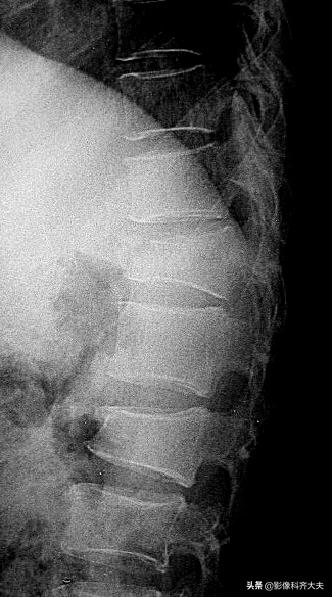

脊柱骨折

多数发生在青壮年,绝大多数都是间接外力所致,直接*力暴**多见于战伤、地震伤,另外肌肉的强力收缩(如破伤风或癫痫)亦可引起。

一般X线平片即可诊断

为了判定有无附件骨折及骨折片进入椎管内的位置需做CT检查,对骨折后脊髓改变的观察需做MRI检查。

X线平片:

可单个发生或多个椎体同时发生。

受累椎体可出现压缩骨折、楔形压缩骨折并椎体前缘游离骨块、前上缘与上位椎体下缘套叠骨折、纵行骨折等形态。

除形态改变外椎体松质小梁骨折嵌入,密度相对较高,表现为椎体面下0.1~1cm或在椎体中部的致密带状影,边缘较模糊。

胸12及腰2楔状变形,胸12椎体前缘可见碎骨片